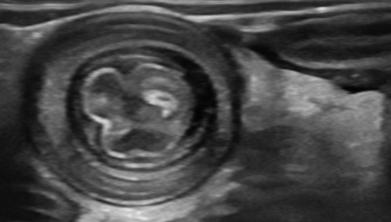

典型超声表现:

· “靶环征”或“同心圆”:在横断面上看到像靶子一样的圆圈,这是肠子套叠的标志性图像。

· “假肾征”:在纵切面看起来像一个肾脏的图像,也是常见表现。